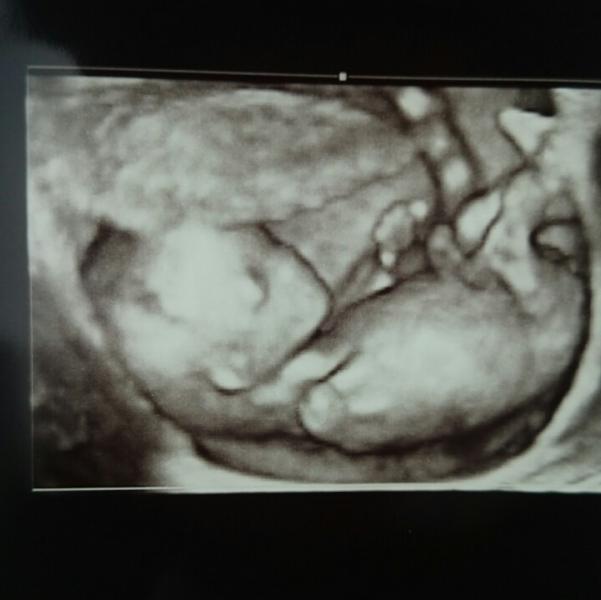

Девочки, сходили на УЗИ! Все отлично) Все в норме) Опережаем срок на один день. ттт Смотрели двумя способами, и через животик и вагинально. Загиб сильный назад. Прикрепление по передней стенке. Малыш такой красивый)) Предположительно девочка)) но наш папа теплит надежду, что там еще что то может отрастет)))

Хотела бы отдельно сказать о Гольцфарб. Он такой крутой и дотошный. Очень долго смотрел. Сердце много раз слушал. В общем я в восторге) ну и фоточка))

@tasenaz, это на Ленина 17, Лотос. Очень рекомендую, может с мужем. Доктор сначала сам смотрит. Потом в конце все рассказывает. У Вас будет индивидуальный экран, он смотрит как в 2Д так и в 3Д. Чувства не описуемые ))